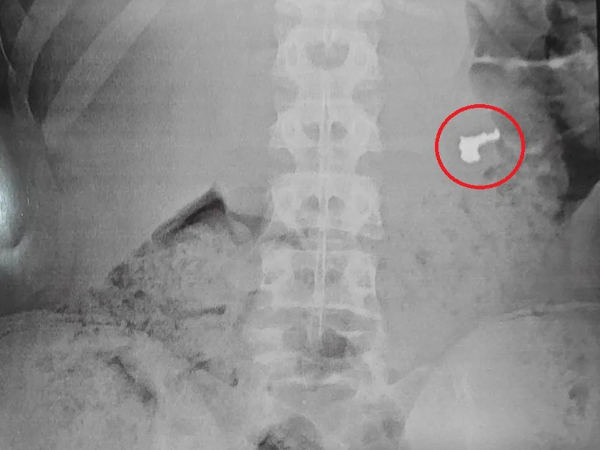

Imagem de Raio-x revela joia no estômago de jovem | Foto: Divulgação

Na unidade de saúde, exames de raio-X foram realizados, e o resultado de um deles identificou a joia roubada.

Na unidade de saúde, exames de raio-X foram realizados, e o resultado de um deles identificou a joia roubada. Os três menores foram encaminhados à Delegacia Sede de Guarujá, onde a ocorrência foi registrada.